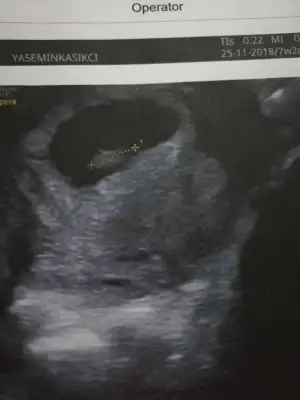

Ypk kuzum aynı foto işte. Karından. Arkadaş öyle diyince buraya da atayım dedim. Bildiğin solda bebek. Kızımın usg sine bakıyorum oda en sağa yapışık. Tam tersi tarafta. Senin usg yi atsana bi 7 haftalık olanı

Çok teşekkür ederim Rabbim gonlunuzden geçeni kabul etsin USG görüntümüz karındanGözün aydın :) kese konumuna göre sağ da mıydı solda mı ? Benim kızım sağdaydı. Bu gebelikte solda. Kızlar Buda kız dedi ama ben erkek hissediyorum![]()

Bak aynı doktor aynı makine bu da kızım 7+2 :) demek istediğim bu

Senin kızlar tersi tarafta mıydı karşılaştırdın mıBak canım benimki solda, senin bebek sağda duruyor

Nuba göre bakılmıştı onda . Kese bu 7 haftalık